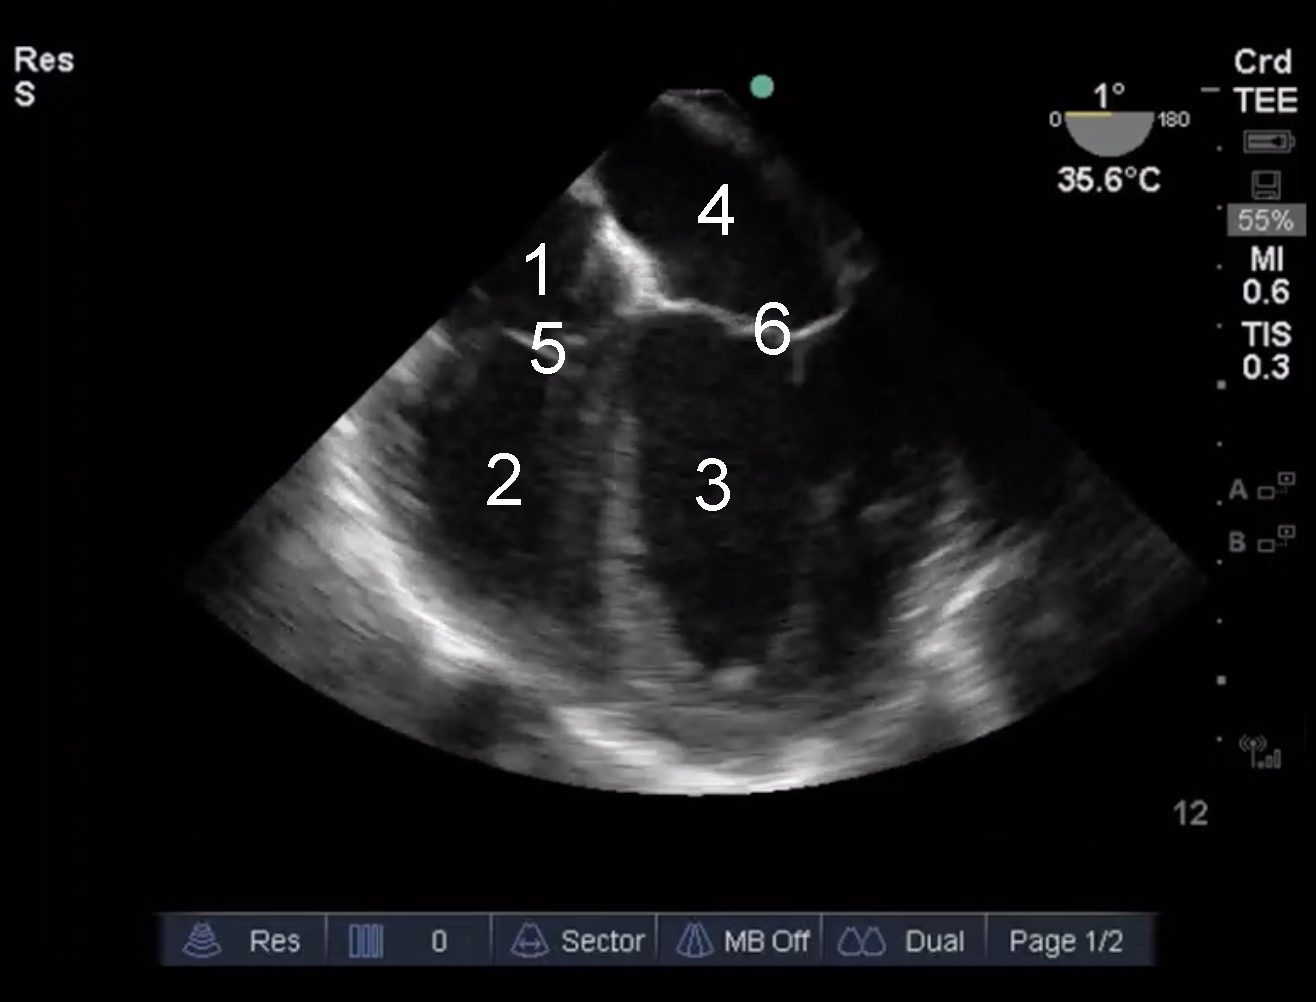

Cardiac 2 TEE Mid Esophageal 4 Chamber Image

1. Right Atrium (RA)

2. Right Ventricle (RV)

3. Left Ventricle (LV)

4. Left Atrium (LA)

5. Tricuspid Valve

6. Mitral Valve